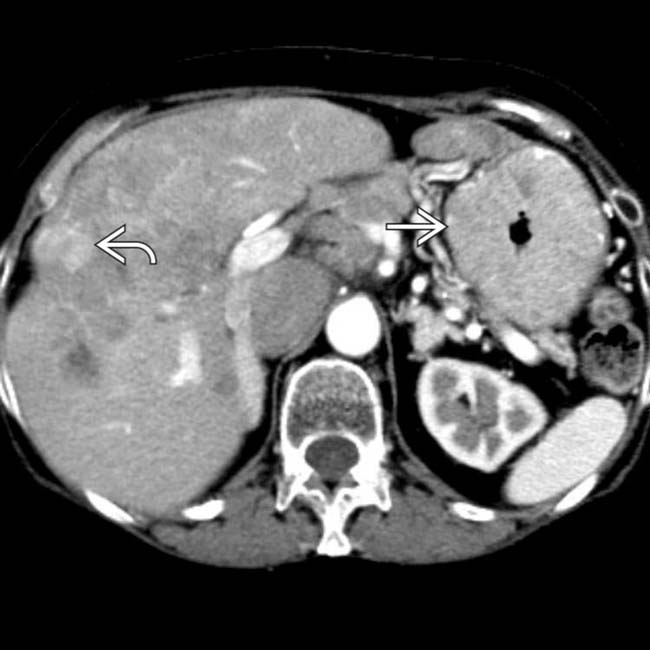

From www.semanticscholar.org

Figure 1 from Diagnosis of the ZollingerEllison syndrome. Semantic Scholar What Causes Zollinger Ellison Syndrome Tumors are masses of cells that continue to grow by overproducing. This excess gastric acid can cause peptic ulcers in your stomach and intestine. People who have zes develop tumors known as. What Causes Zollinger Ellison Syndrome.